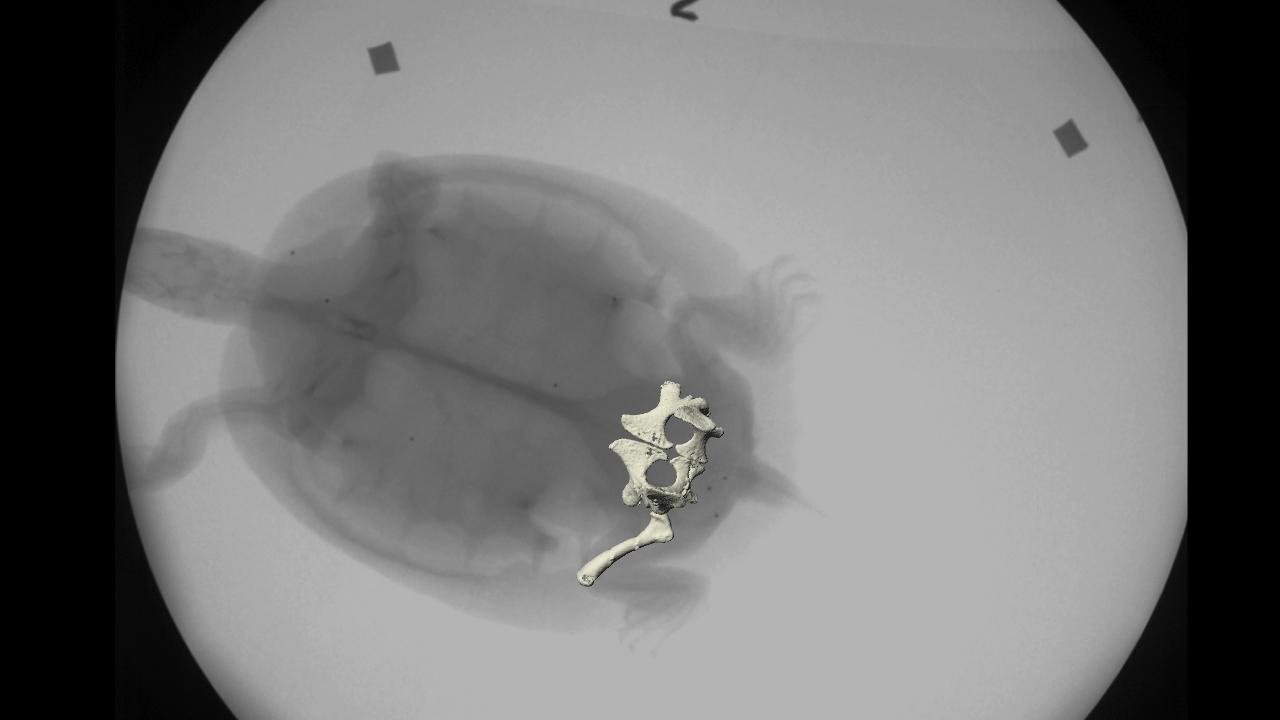

Radioskopia dhe tomografia japin imazhe brenda çdo gjallese. Por, ato nuk mund të tregojnë me saktësi se si muskujt dhe kockat punojnë së bashku.

Shkencëtarët e këtij institucioni, me anë të teknologjive të reja, kanë paraqitur paisjen e quajtur “XROMM” – mënyrë e re për të parë çdo gjë brenda trupave të njerëzve dhe kafshëve.